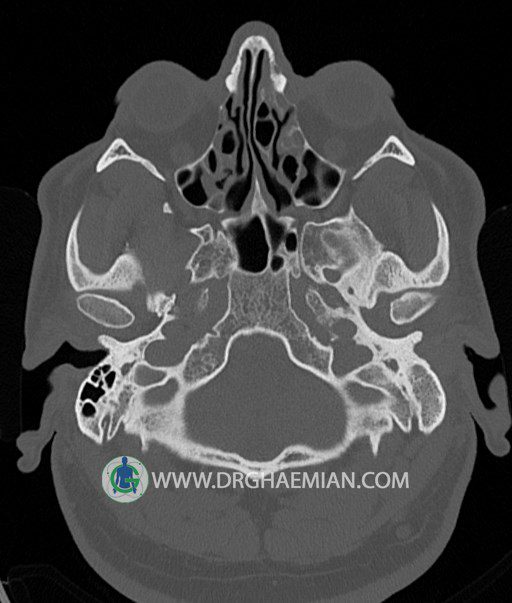

سی تی اسکن گوش داخلی به رادیولوژیست اجازه می دهد تا سطوح مختلف، یا اسلایس هایی از استخوان های که از جمجه به گوش می روند را از طریق امواج ایکس چرخشی مشاهده کند. در این کیس اودیت مدیا، ماستوئیدیت مزمن، اوتیت خارجی، انحراف سپتوم بینی، کونکا بولوزا و افزایش ضخامت سینوس ها مشاهده می شود.

در HRCT از استخوان تمپورال با مقاطع آگزيال ، ساژيتال و کرونال ظريف ( 0.6 mm ) :

– نماي کوکلهآي دو طرف با 2.5 دور گردش مجرا

– نماي cochlear aqueduct

– نماي semicircular canal خلفي ، لترال ، فوقاني و وستيبول

– استخوانچه هاي گوش داخلي شامل malleus ، incus و stapes (دنسيتي و رديف استخوانچه ها )

– نماي oval window و round window ، tympanic cavity ، attic و کانال گوش داخلي

– کانال عصب فاشيال و مسير ان از ناحيه کانال گوش داخلي ، geniculate ganglion تا محل خروج ان از stylomastoid foramen

– نماي tympanic membrane ، کانال ICA ، بولب جوگولار دو طرف

در حد طبيعي است .

– اپاسيتي گوش مياني چپ ناشي از وجود دانسيته نسج نرمي دراطراف استخوانچه ها همراه با اروژن اسکوتوم و

استخوانچه ها بدون جابجايي در رديف استخوانچه ها مشهود است که مطرح کننده اوتيت مديا همراه با نشانه

هاي مشکوک به کولستئاتوم مي باشد .

– اپاسيتي و اسکلروزيس ماستوئيد چپ نشانه ماستوئيديت مزمن

– اپاسيتي کانال گوش خارجي ناشي از دانسيتي نسج نرمي مطرح کننده external otitis

– انحراف سپتوم مياني بيني به راست

– کونکا بولوزا در کونکاي مياني چپ و

– افزايش ضخامت مخاطي در سينوس هاي اتموئيد و ماگزيلاري

اپاسيته